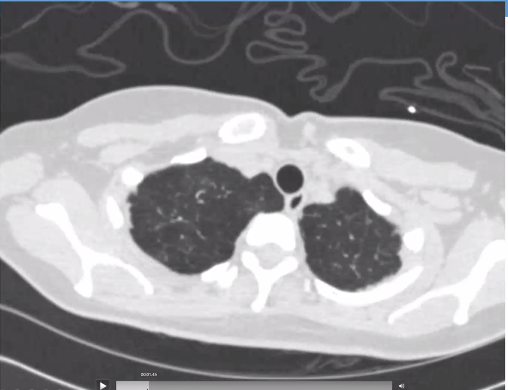

Lots of mosaic attenuation!

She goes to the ED and gets another CT... mosaicism is still there but now she has a new bilateral pleural effusions and interlobular septal thickening and atelectasis.

Whoops - seem to have accidentally started a new thread for the rest of the case. Case continues with the remainder of the HPI in image below, followed by CT scan here: